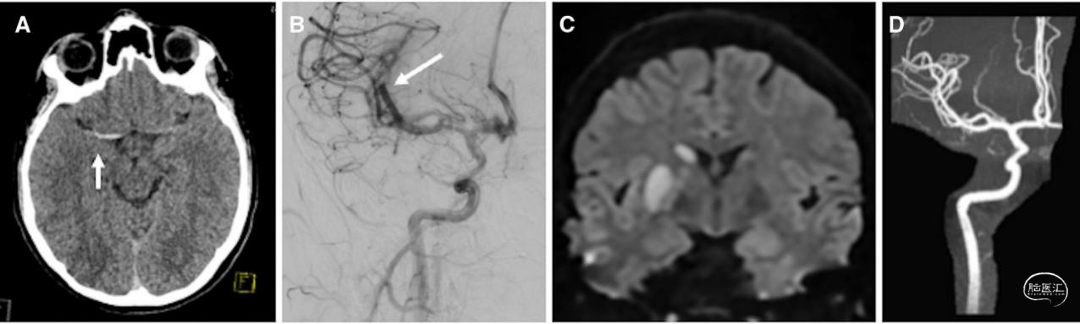

患者男,14岁,右利手,有慢性回肠炎病史,因癫痫发作后出现意识模糊、左侧肢体无力、右侧凝视偏移就诊。外院就诊时,患者美国国立卫生研究院卒中量表(NIHSS)评分为9分。头颈部CT血管成像(CTA)示右侧颈内动脉(ICA)末端至大脑中动脉(MCA)近端闭塞(图1A)。

发病3.5小时,患者接受静脉阿替普酶溶栓治疗(0.9mg/kg),并迅速转至具备儿童神经介入放射条件的医院。初始血管造影示右侧ICA已再通,但MCA M2段近端(优势分支)及大脑前动脉(ACA)A2段闭塞(图1B)。发病5小时,通过血管内取栓术成功取出M2段血栓,MCA完全再通,脑梗死溶栓(TICI)分级3级;未尝试处理A2段血栓。随后患者转入儿科重症监护室接受严密神经功能监测。

卒中后第1天,患者NIHSS评分降至1分(轻度面部不对称);溶栓后24小时头颅磁共振成像及血管成像(MRI/MRA)示右侧基底节、尾状核、脑岛及额叶岛盖区梗死(图1C),右侧MCA分支血流通畅(图1D)。予阿司匹林325mg/日作为卒中二级预防,第5天出院时剂量调整为81mg/日。经食管超声心动图检查示卵圆孔未闭,结合患者回肠炎相关高凝状态,考虑卒中病因为反常栓塞。3个月随访时,患者已重返校园,神经功能基本恢复至发病前水平,仅存在轻微认知改变及活动后左侧肢体轻度无力。

病例1为符合2026年AIS指南推荐的超急性期治疗适应证的青少年病例,最终患者获得极佳结局。CT/CTA仍是多数医院最可行、最快捷的影像学检查手段。对于疑似LVO儿童患者,若等待MRI/MRA检查会延误救治,即便儿童患者也可行CT/CTA(2026年AIS指南2a类推荐)。